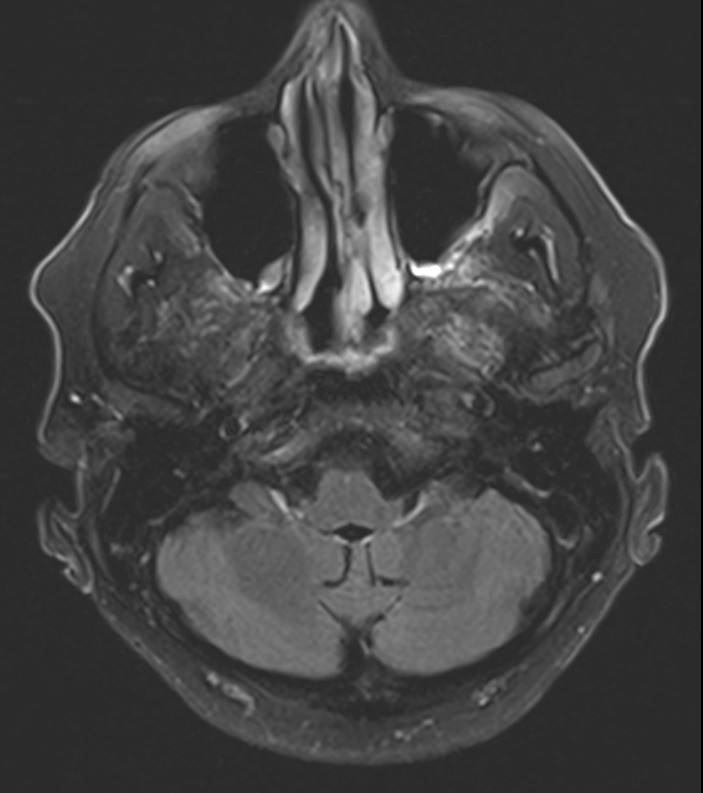

A computed tomography (CT) scan showed an age-indeterminant lacunar infarct in the pons. For diagnostic clarity, magnetic resonance imaging (MRI) of the brain was ordered, the results of which showed symmetric increased T2-weighted fluid-attenuated inversion recovery (FLAIR) signal within the dentate nucleus, periaqueductal gray, tectum, red nucleus, and splenium of the corpus collosum, consistent with toxic acquired metabolic encephalopathy (Figures 2 and 3).

Figure 3. Symmetric Increased T2-FLAIR MRI signal along the splenium.

After 3 days, the patient’s condition began to improve, and on day 5, the color of his urine returned to normal. Upon discharge, the man’s psychiatric symptoms resolved, although the neuropathic symptoms persisted. At 4 months’ follow-up, brain MRI showed resolution of abnormal findings (Figures 4 and 5). The patient and his wife both reported that he had no more psychiatric symptoms; however, his baseline peripheral neuropathy, similar to that seen at discharge, had persisted.

Figure 5. Resolution of increased T2-FLAIR signal described in Figure 3, 4 months after discontinuation of metronidazole.